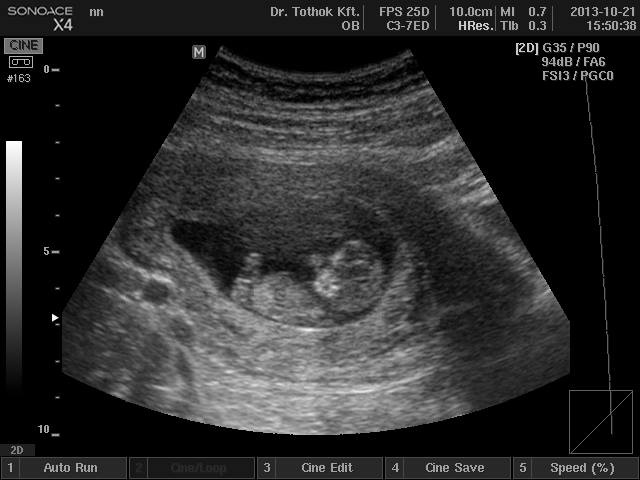

nagyon nagyon cuki, micsoda kis babaforma máris, láttam már párszor ilyet, de mindig meglep ![]()